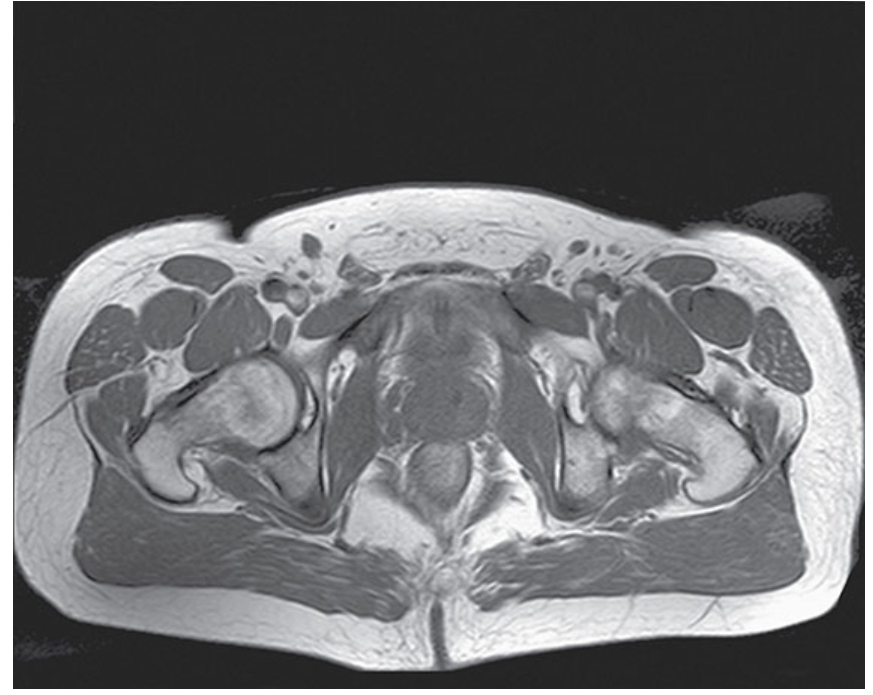

What does this image show?

Axial T1-weighted TSE image of a male pelvis